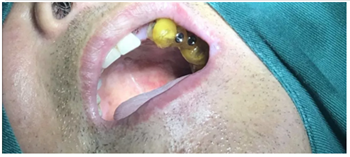

術(shù)前口內(nèi)試戴種植手術(shù)導(dǎo)板